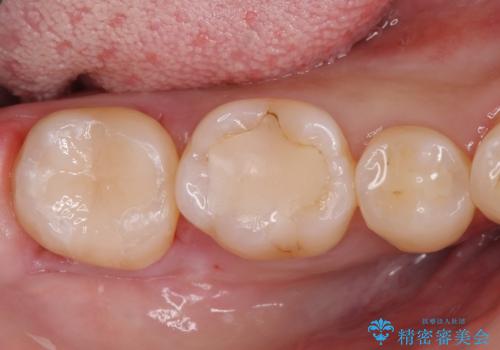

欠けてしまった奥歯 セラミッククラウンとセラミックインレーによるむし歯治療